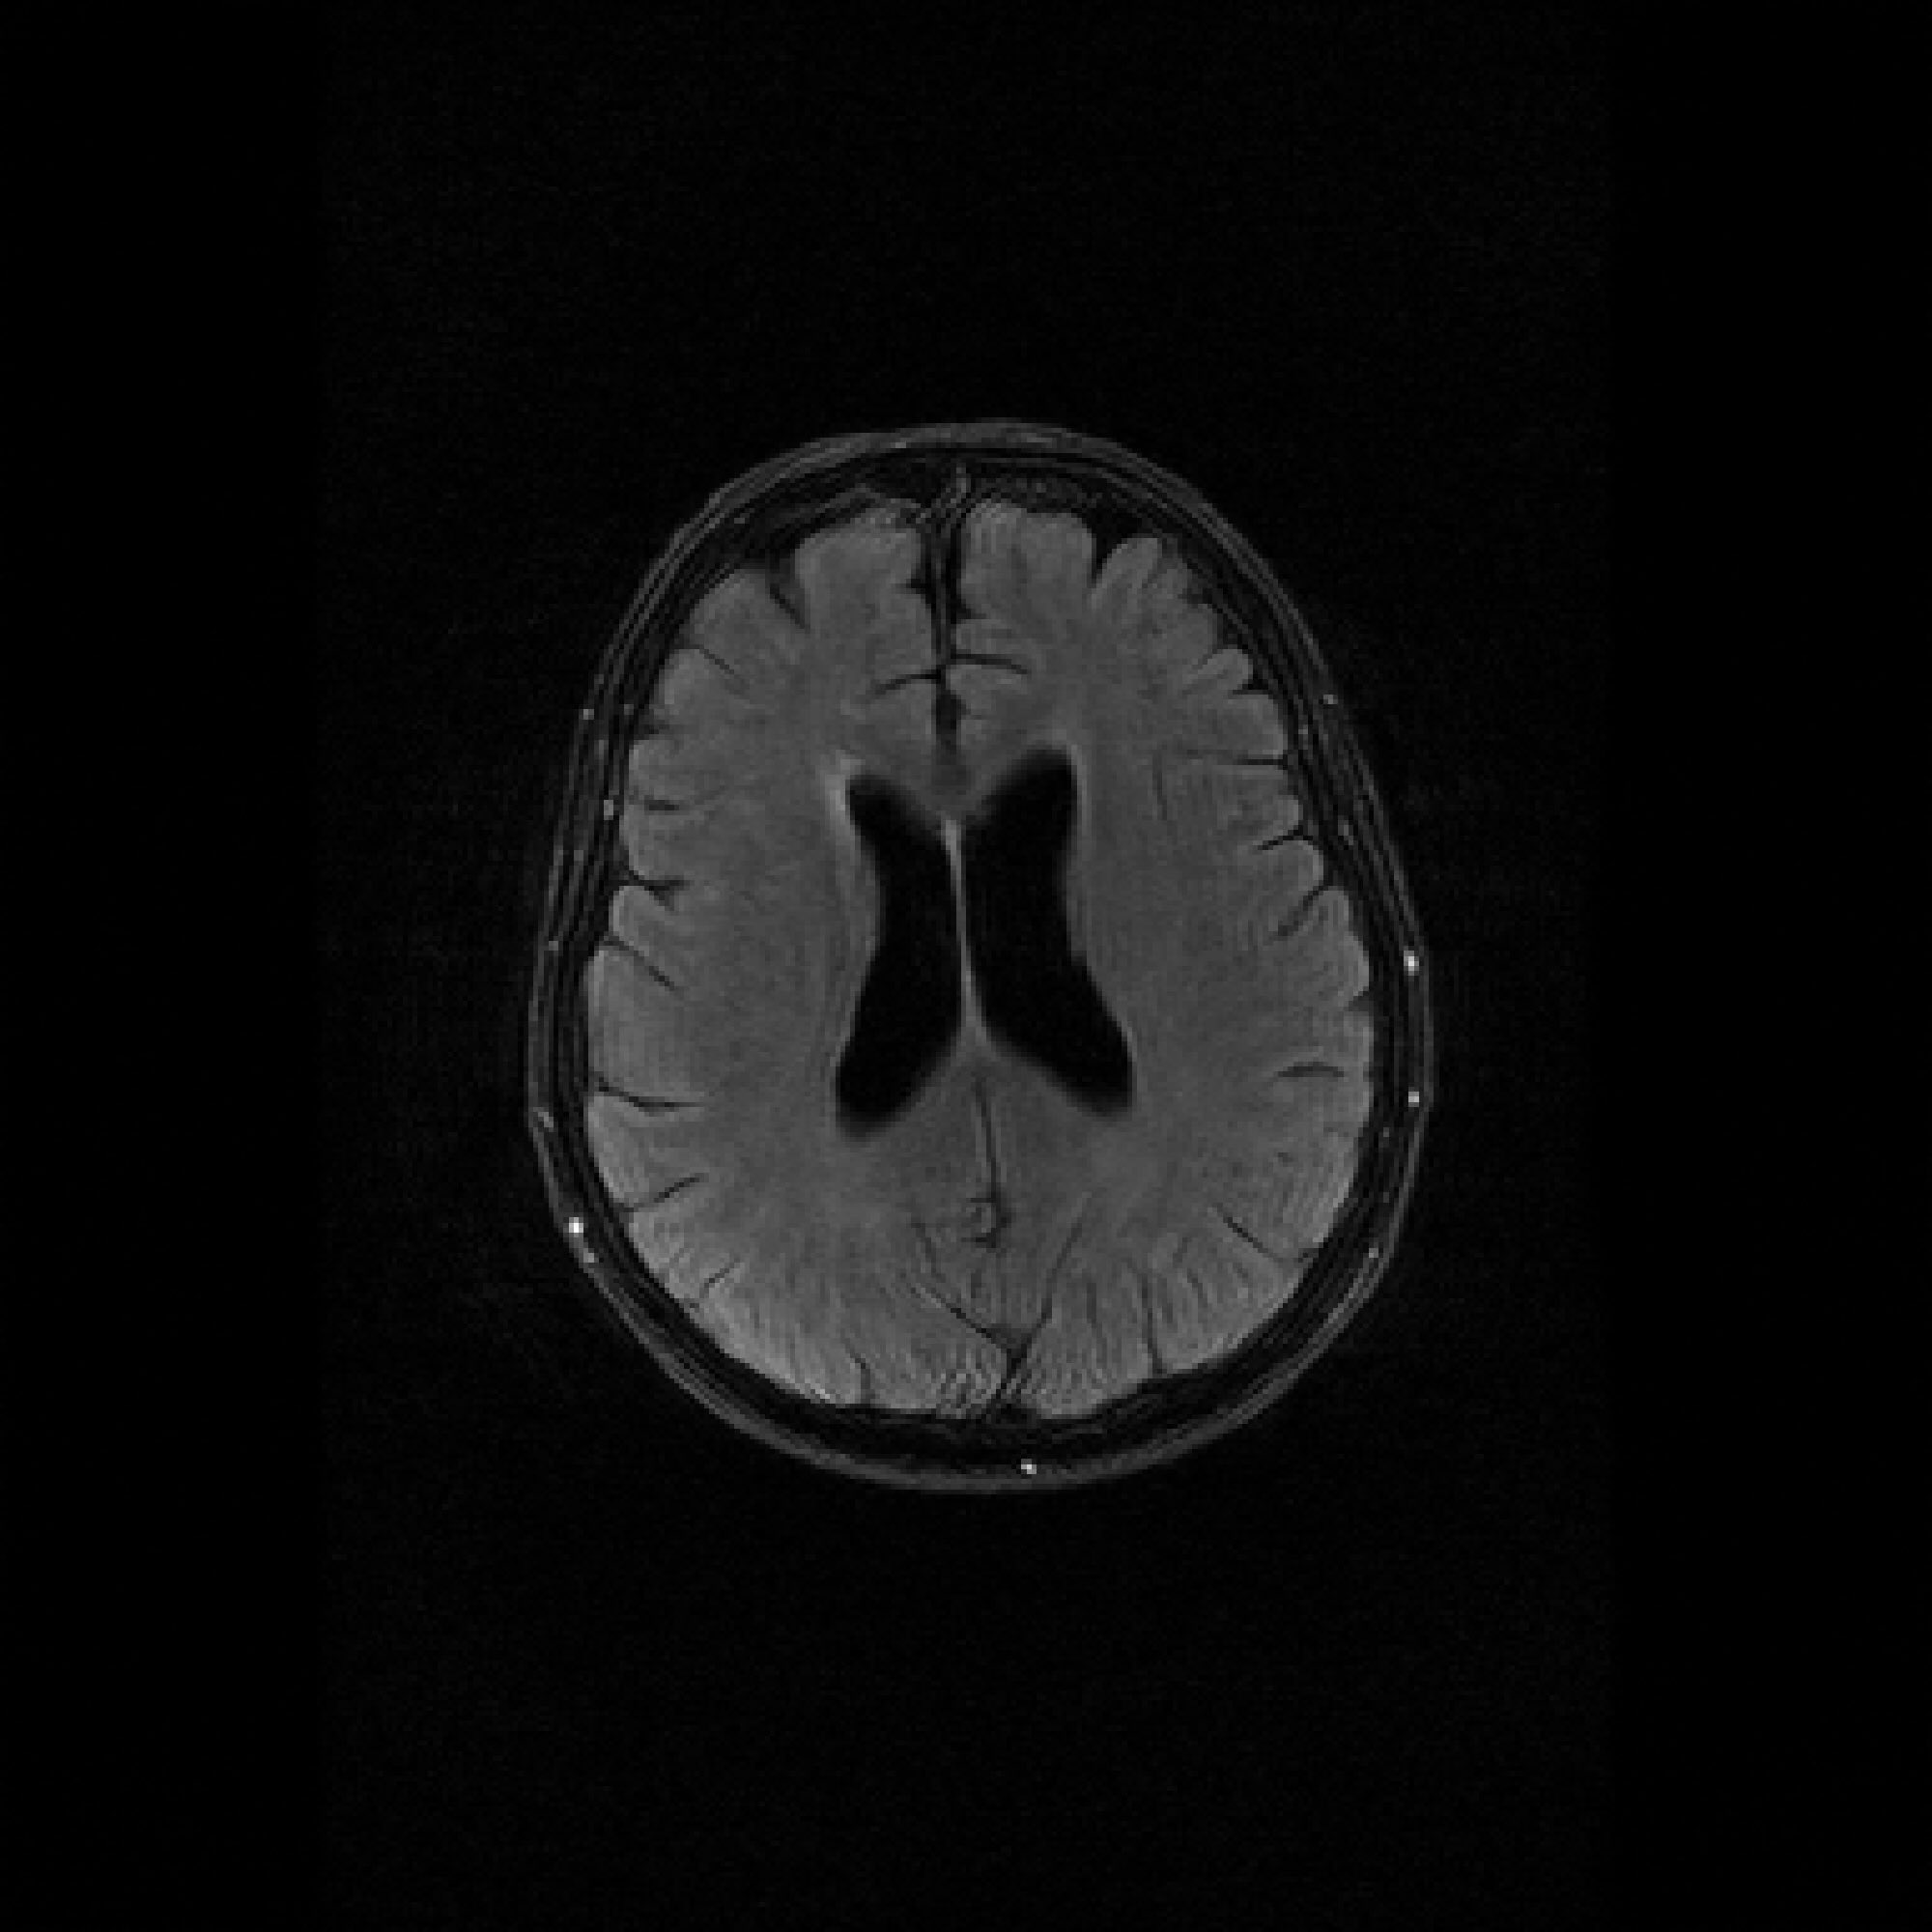

Refer to caption

Figure 3: Pixel-wise standard deviations of reconstructions across 10 random k-space sampling masks (R=7R=7) of the same slice. Top to Bottom: models trained on 100, 500, and 1000 slices. PaDIS-MRI consistently exhibits lower pixel-wise variance (fewer bright regions) than FastMRI-EDM across training sizes and contrast types, indicating more stable reconstruction.

Figure 3 visualizes these standard deviation maps, with brighter regions indicating higher variability between reconstructions. Across the 100-slice, 500-slice, and 1000-slice training regimes, PaDIS-MRI exhibits noticeably lower uncertainty compared to FastMRI-EDM, with the largest differences occurring at the smaller training dataset sizes. This suggests that decomposing the reconstruction problem into localized patches enables more stable learning of anatomical features, resulting in more reliable and consistent predictions from limited training data.